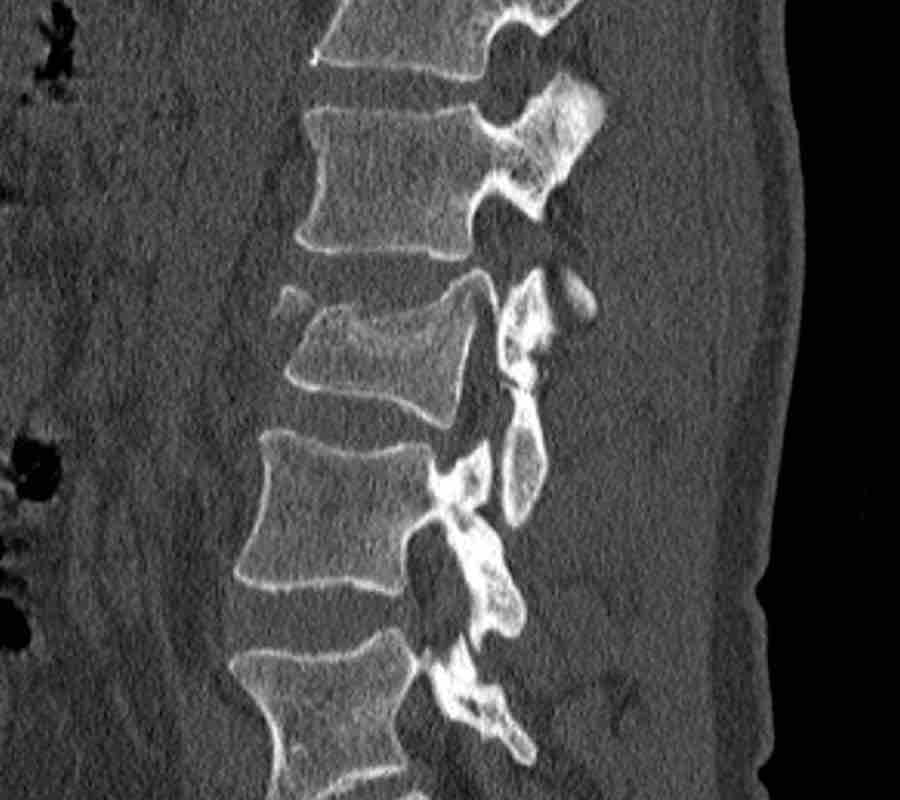

Findings:

- No C or B injury

- Fractures vertebral body with involvement of upper endplate (1 point) and posterior wall (2 points)

Conclusion

Injury type A3